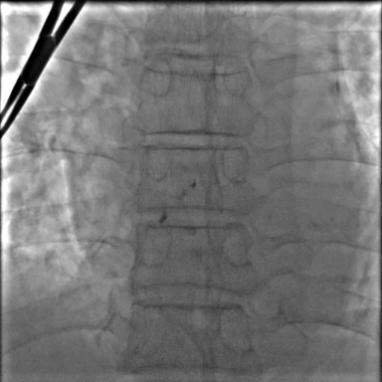

5月10日,心血管内科团队按照计划对老冯进行了手术。术中顺利穿刺左侧锁骨下静脉,经TIG导管、6F JR4导管顺利操作导丝通过卵圆孔进入左上肺静脉。虽然遇上加硬导丝送至左上肺静脉的困难,但团队迅速调整策略,送入260cm J形导丝,随后缓慢推送手工塑形后的180°8F输送鞘并顺利通过,送入并释放18*25mm卵圆孔未闭封堵器。通过透视及超声评估,封堵效果满意。

介入封堵过程:

a.导丝通过卵圆孔进入左上肺静脉;

b.输送鞘通过卵圆孔;

c.封堵器释放后